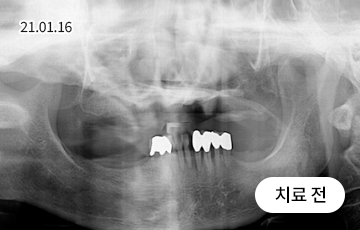

치아의 정출 + 임플란트

정출된 치아에 그냥 심으면 안됩니다.

치아가 소실된 상태로 오래 방치하면, 치아가 아래로 내려오거나 위로 솟구칠 수 있는데, 이를 정출이라고 부릅니다.

정출된 치아를 그대로 두고 임플란트를 심으면 치아 대합이 맞지 않고 환자에게 올바른 치료가 될 수 없기 때문에

임플란트 치료와 더불어 치아교정 또는 크라운 등의 보철치료를 할 수 있습니다.